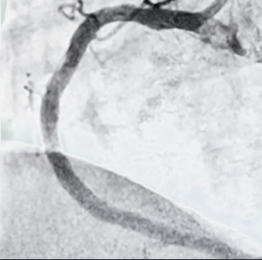

医生在接诊。